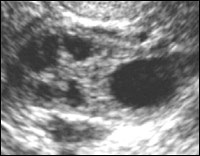

În faza proliferativă timpurie (5-7 zile ale ciclului) endometrul are o ecogenitatea relativ scăzută și uniformă ecostructură. game grosime de 3-6 mm, o medie de 5 mm [3]. In centrul M-ecou chiar și în această perioadă poate fi determinată prin linia hiperecogen subțire care reprezintă limita dintre foile din față și din spate ale endometrului (Fig. 1).

proliferarea timpurie.

endometru